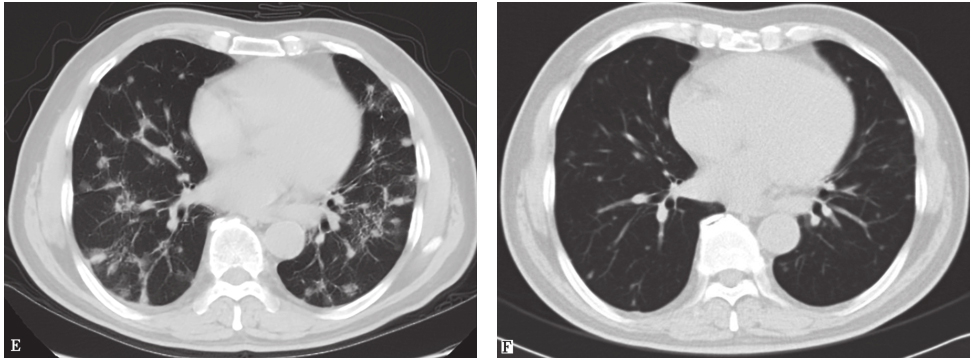

病例Ⅰ入院后体温正常,咳嗽、气短症状较前好转,于2013年8月24日复查胸部CT,见肺部病变较前明显吸收(图4);病例Ⅱ口服伊曲康唑1个月后出现甲状腺功能低下而停用,发病7个月后复查胸部CT,见双肺结节亦明显吸收(图5)。

图5病例Ⅱ治疗后复查胸部CT表现

2013年1月28日查胸部CT(A、C、E)示双肺多发结节性病变;发病7个月后复查胸部CT(B、D、F)示双肺结节影较前明显吸收